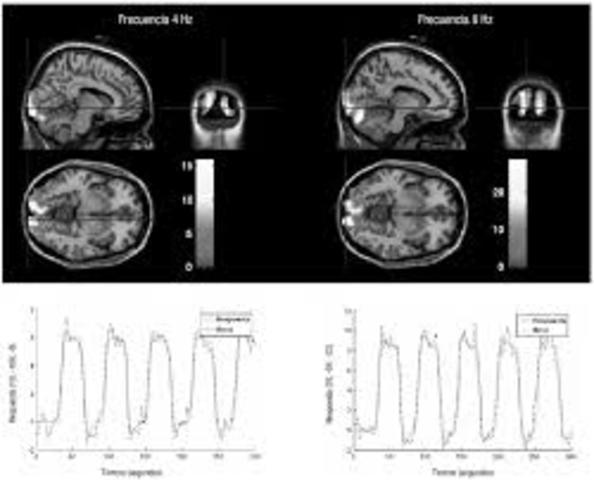

• Resonancia Magnética Funcional

Resonancia Magnética Funcional

La Resonancia Magnética Funcional permite medir el metabolismo regional del cerebro.